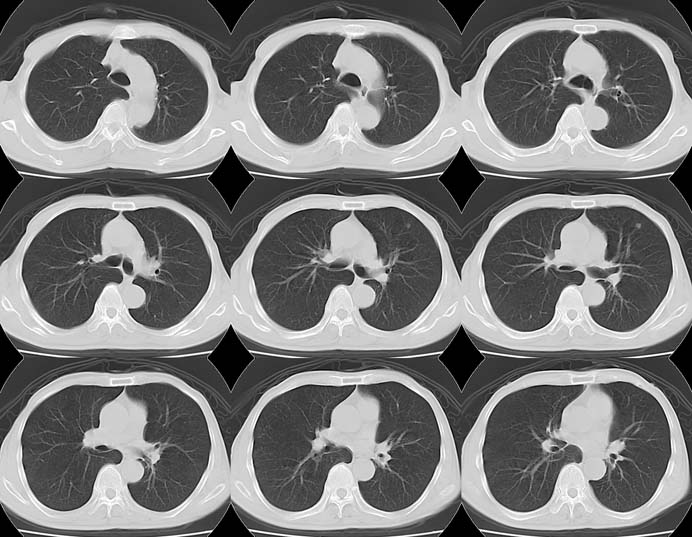

Lung Cancer: Adenocarcinoma:"High-speed screening mode."

8mmx4, Pitch 6, 384mm, 4-seconds, 150-mAs: